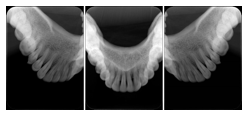

Intra-oral radiography typically involves acquisition of multiple images of various parts of the dentition. Many digital radiographic systems offer customized templates that are used for displaying the images in a study on the screen. These templates may also be referred to as mounts or view sets. The Structured Display Object represents a standard method of encoding and exchanging the layout and intended display of Structured Displays. A structured display object created in this manner could be stored with a study and exchanged with images to allow for complete reproduction of the original exam.

1. A patient visits a General Dentist where a Full Mouth Series Exam with 18 images is acquired. The dentist observes severe bone loss and refers the patient to a Periodontist. The 18 images from the Full Mouth Series along with a Structured Display are copied to a DICOM Interchange CD and sent with the patient to see the specialist. The Periodontist uses the CD to open the exam in his Dental Radiographic Software and consults via phone with the General Dentist. Both are able to observe the same exam showing the images on each user's display using the exact same layout.

Intra-oral Full Mouth Series Structured Display

Figure OO-1. Intra-oral Full Mouth Series Structured Display